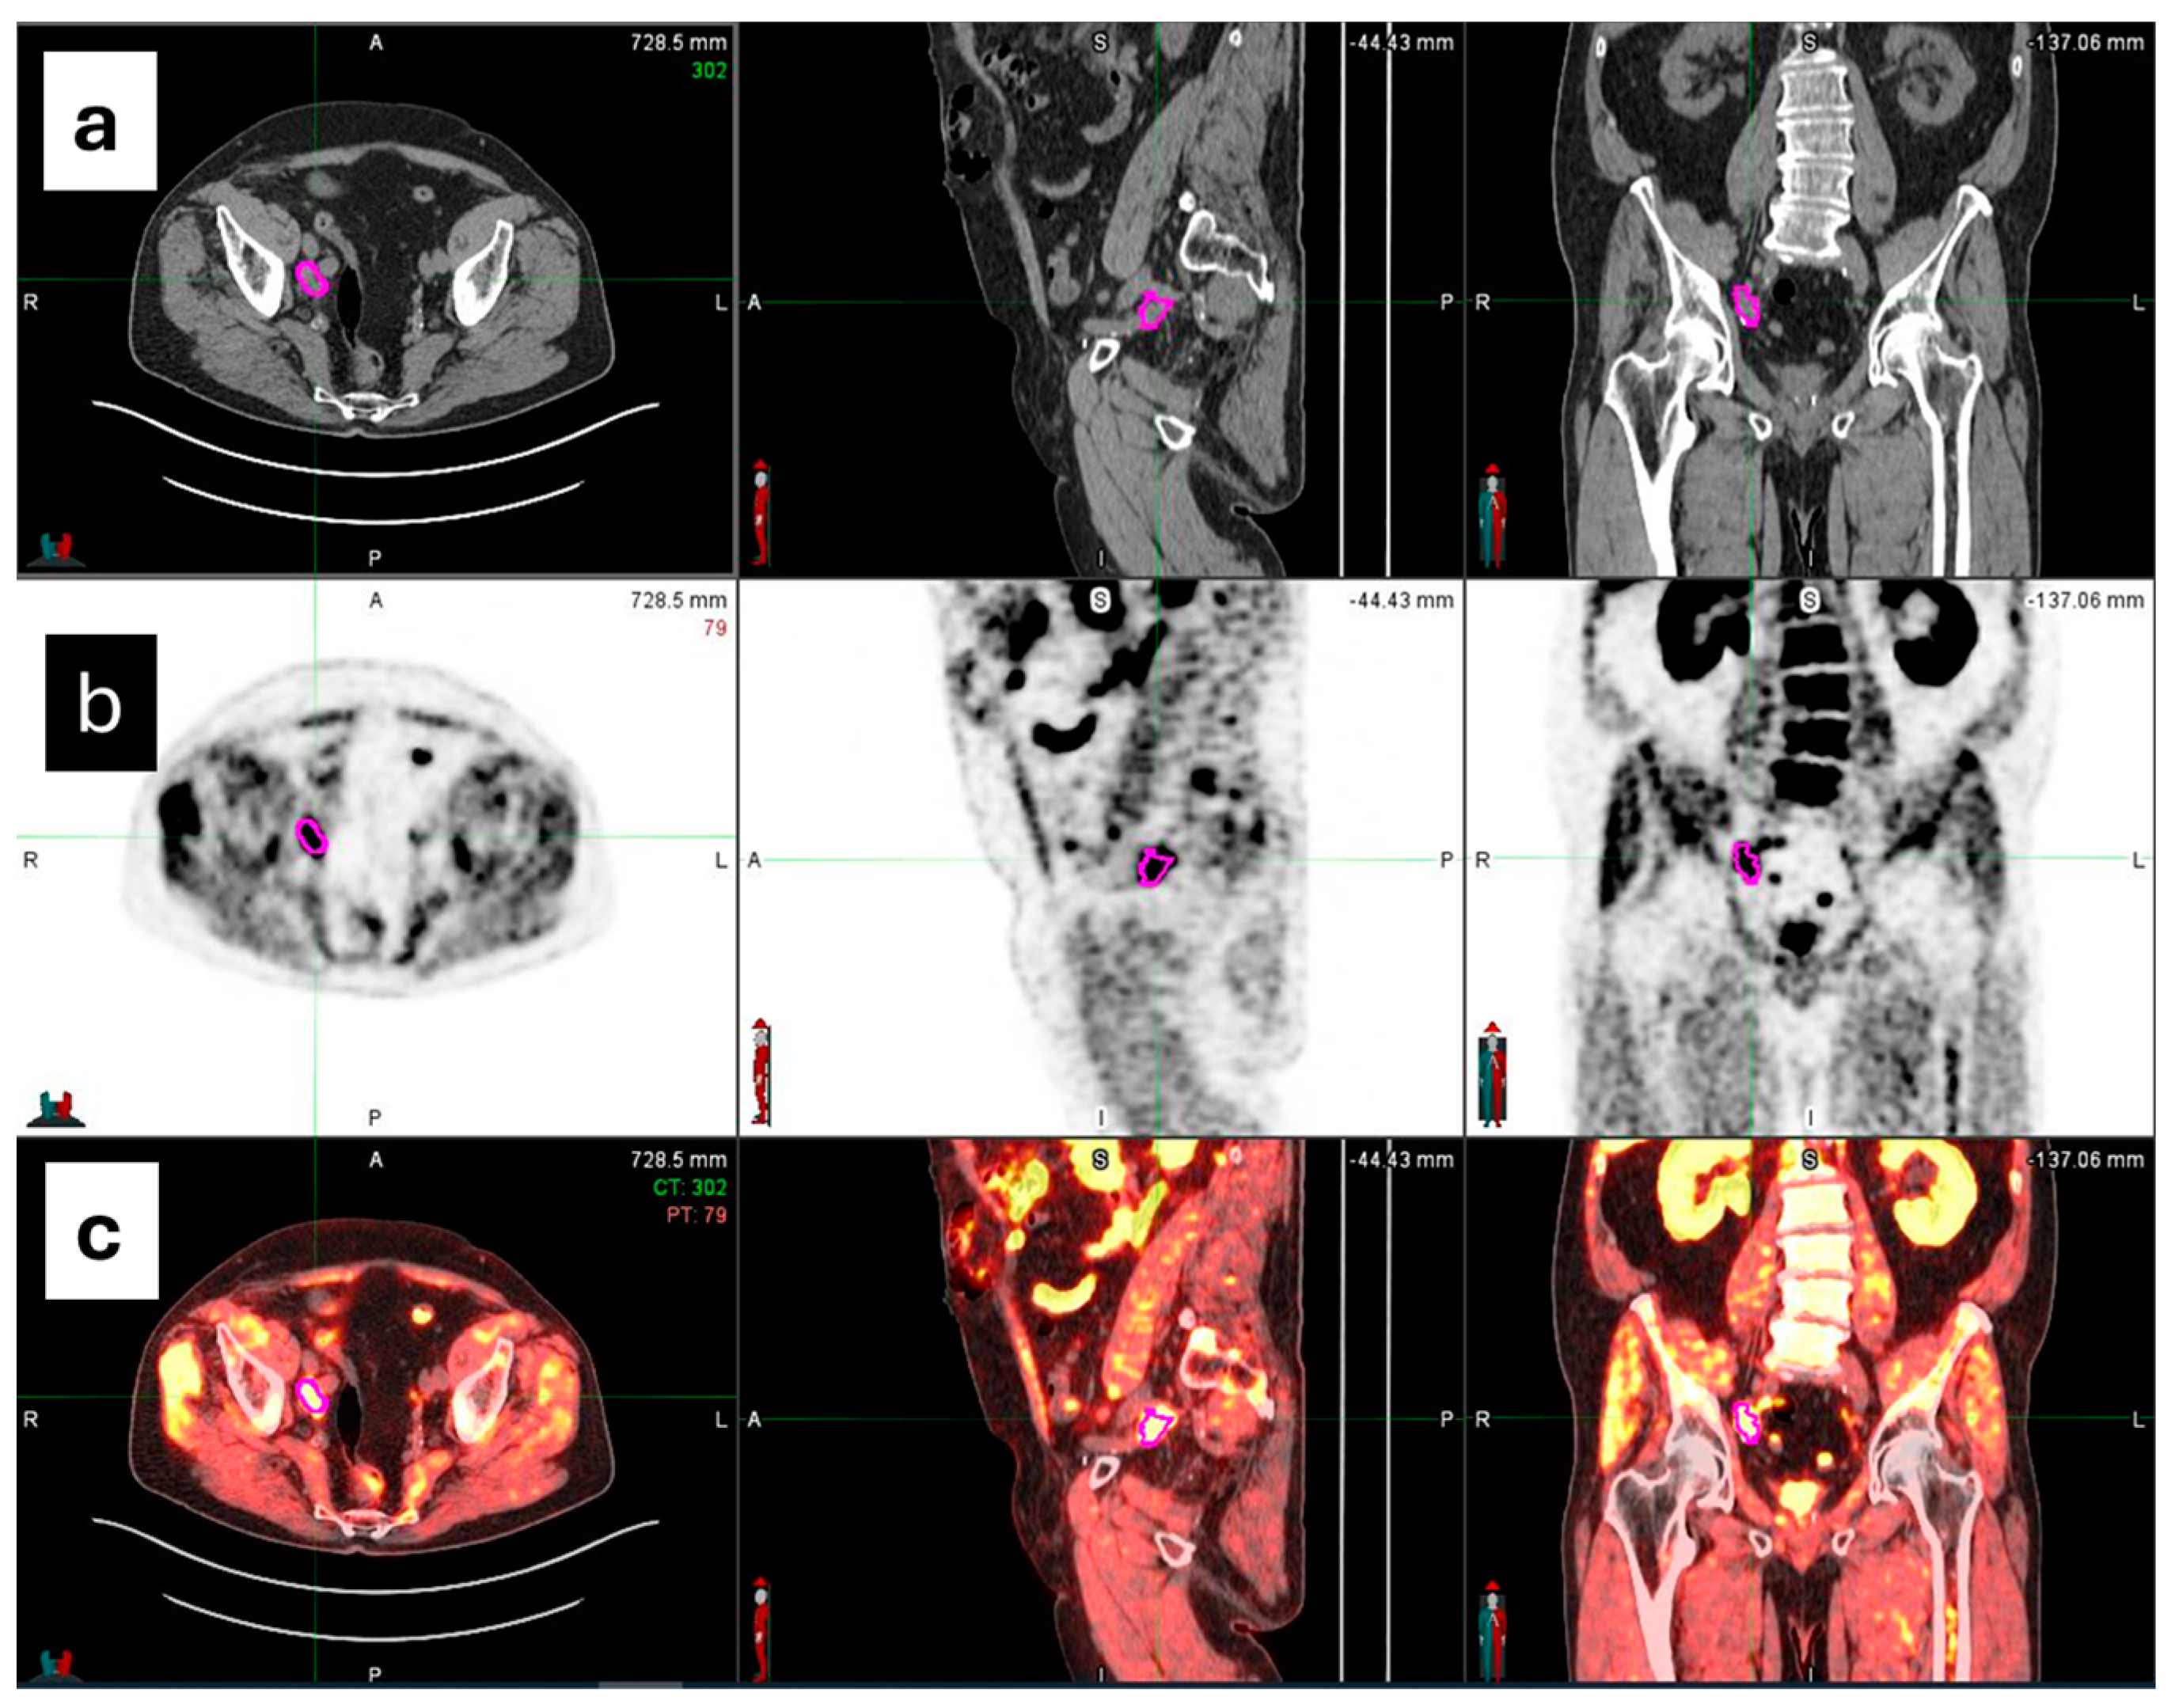

2.4. Image Segmentation and Feature Extraction